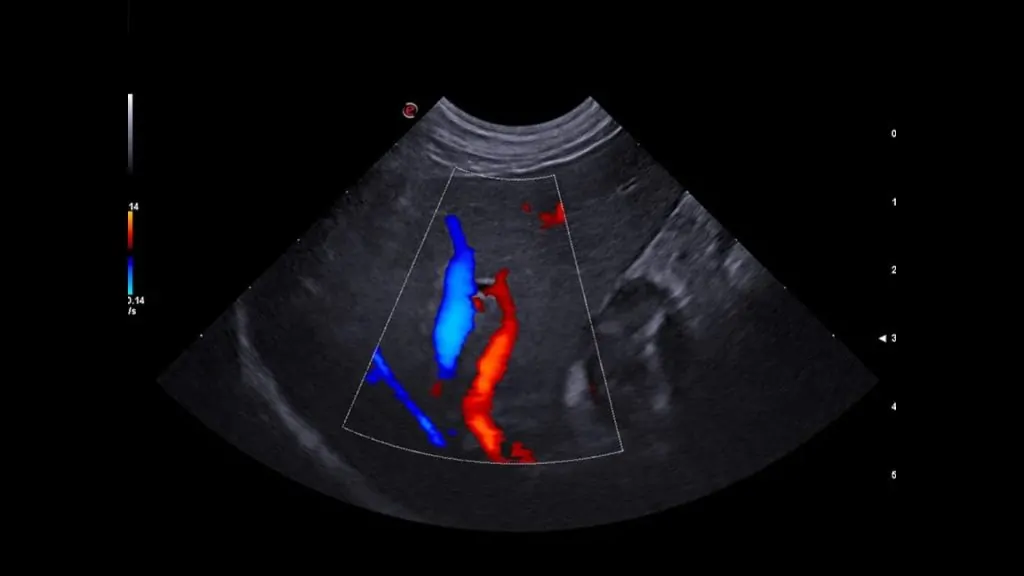

• Büyük damarlarda trombüs/emboli şüphesi gibi vasküler değerlendirmeler

• Gerekli görülen durumlarda Doppler USG ile kan akımı analizi yapılabilir.